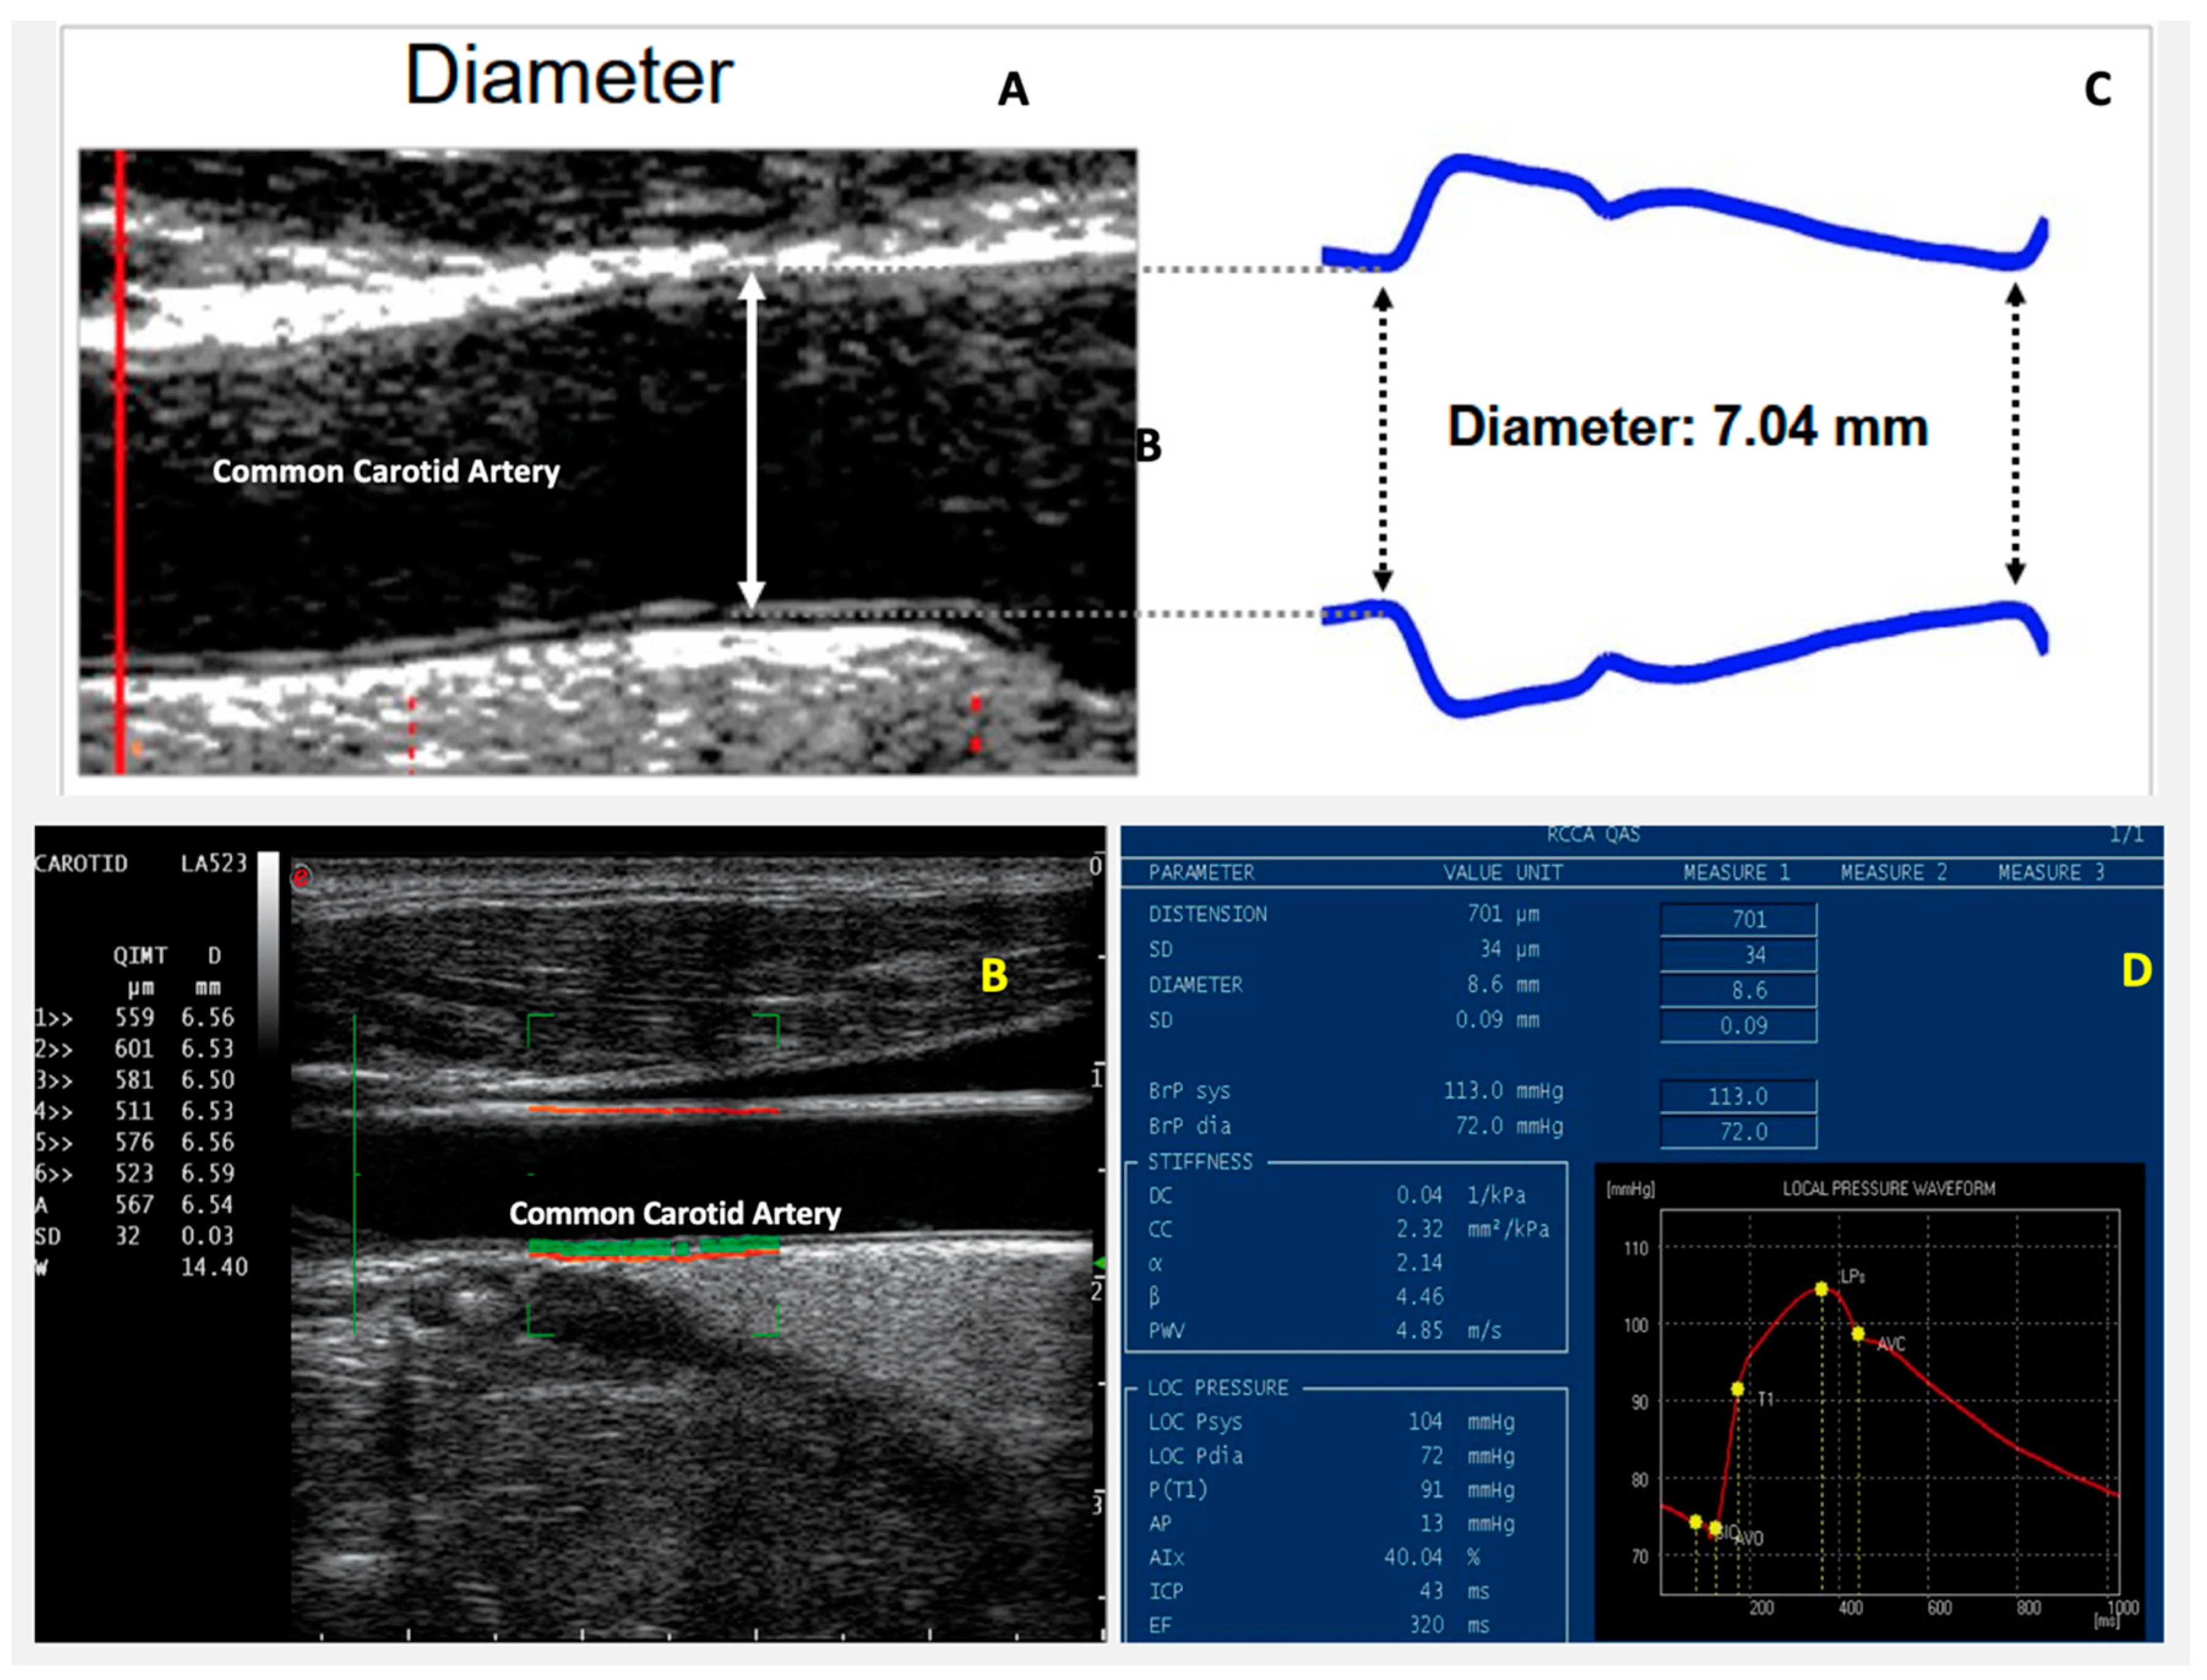

7. Arterial Stiffness

Role of Arterial Stiffness in IHD